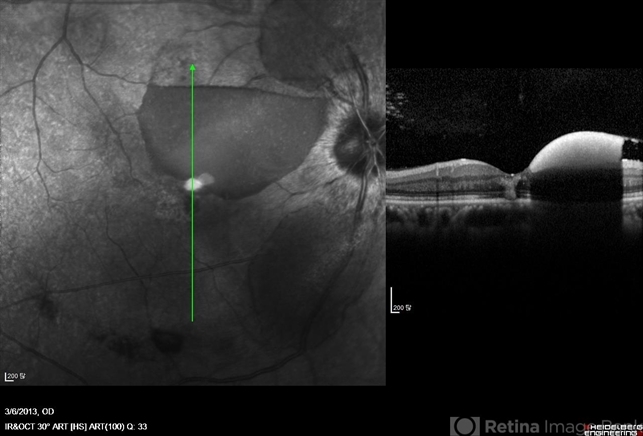

- Terson's Syndrome, sub-inner limiting membrane hemorrhage

- OCT image of a 56-year-old woman with a sub-ILM hemorrhage. She has subarachnoid hemorrhage.